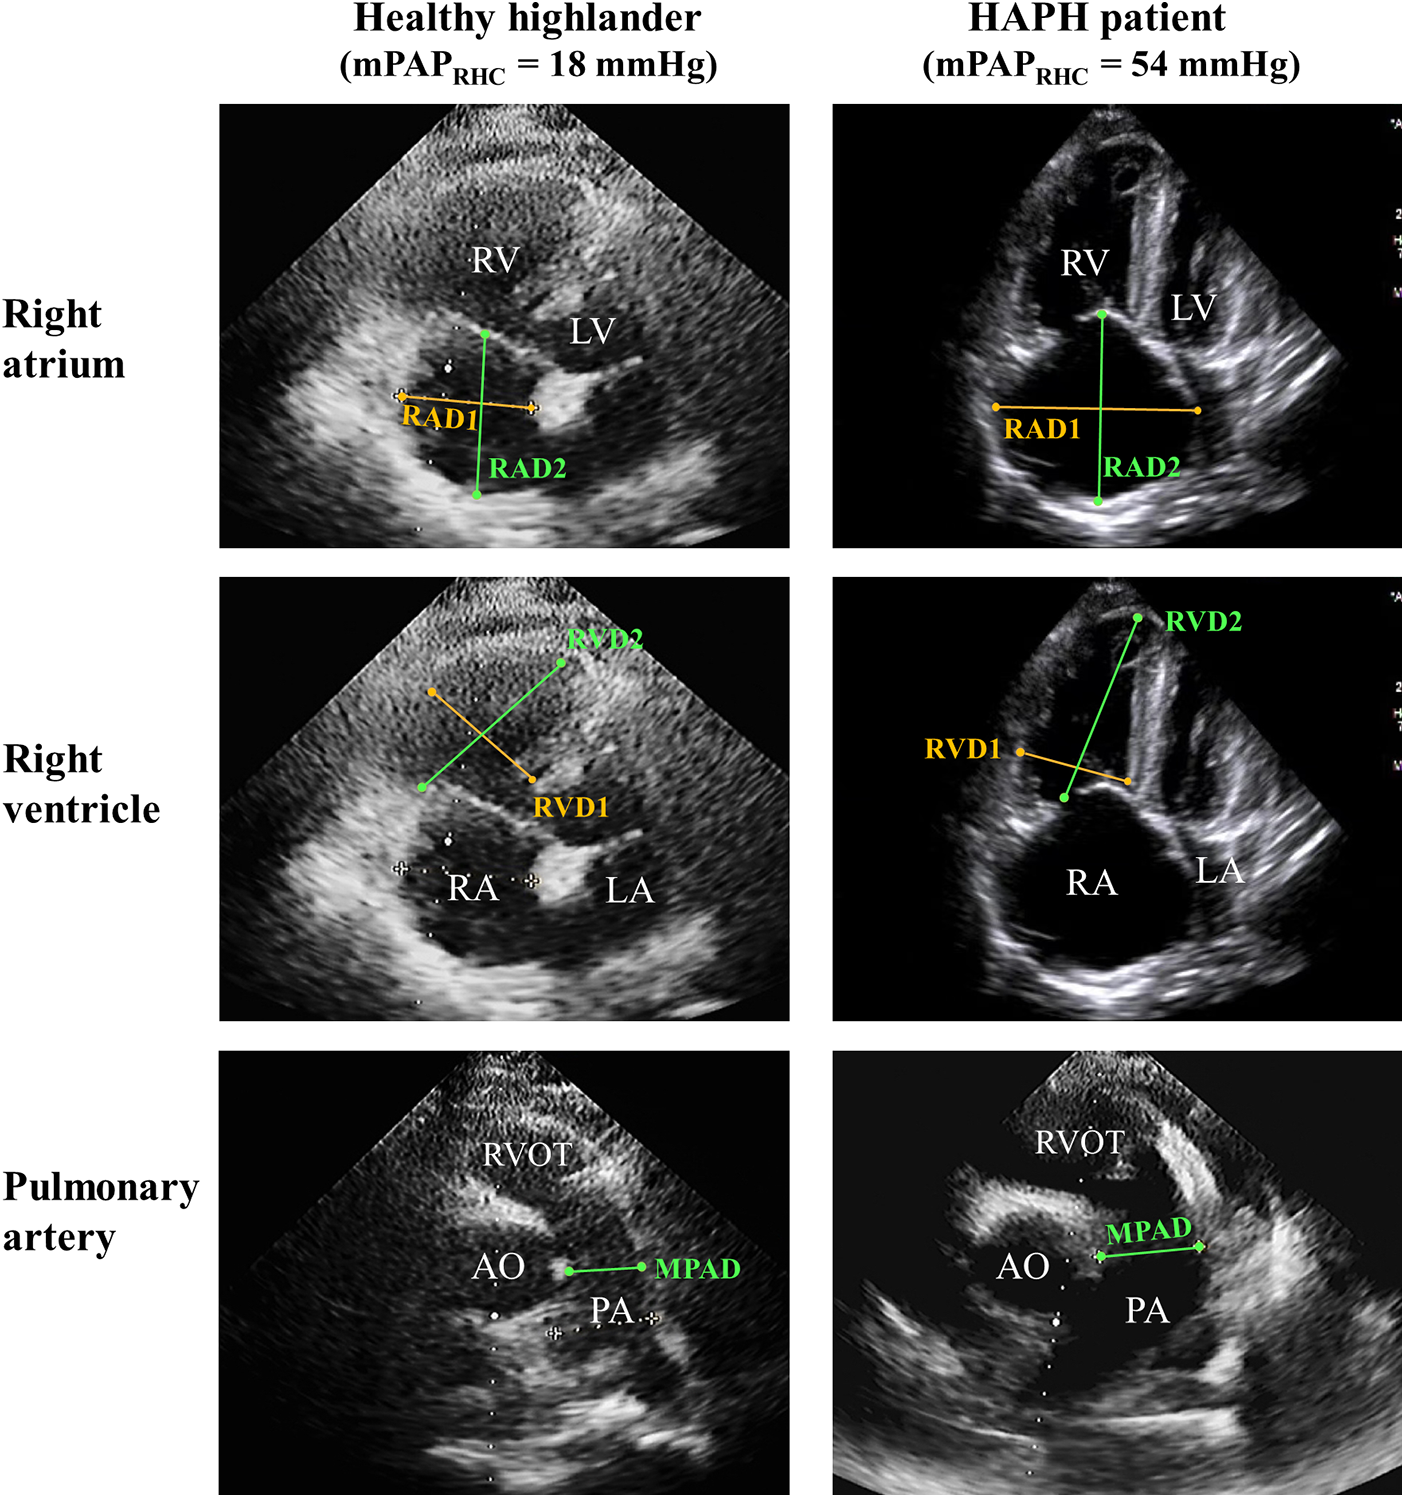

The representative imaging for parameters of the right atrium and ventricle is shown in Figure 1. Patients with abnormal mPAPPredicted were more likely to exhibit several echocardiographic abnormalities, including an enlarged right atrium and ventricle in both transverse and vertical dimensions (p for trend <0.01), a dilated main pulmonary artery (p for trend <0.01), and an elevated TRPG and PASP (p for trend <0.05). However, there were no significant differences in left heart diameter and LVEF among the three groups with varying mPAPPredicted. These findings indicated that HAPH patients are more likely to display signs of right heart dysfunction, as evidenced by echocardiography (p for trend <0.05; illustrated in Table 2). Further details regarding the between-group differences and 95% CIs for echocardiography characteristics are provided in Supplementary Table 3.

Figure 1

Representative imaging of the echocardiographic sign of right heart dysfunction. Right ventricle-focused apical four-chamber view and pulmonic valve-focused parasternal short-axis view of HH and HAPH patients. PA, pulmonary artery; RAD1, transverse diameter of right atrium; RAD2, vertical diameter of right atrium; RVD1, transverse diameter of right ventricle; RVD2, vertical diameter of right ventricle.